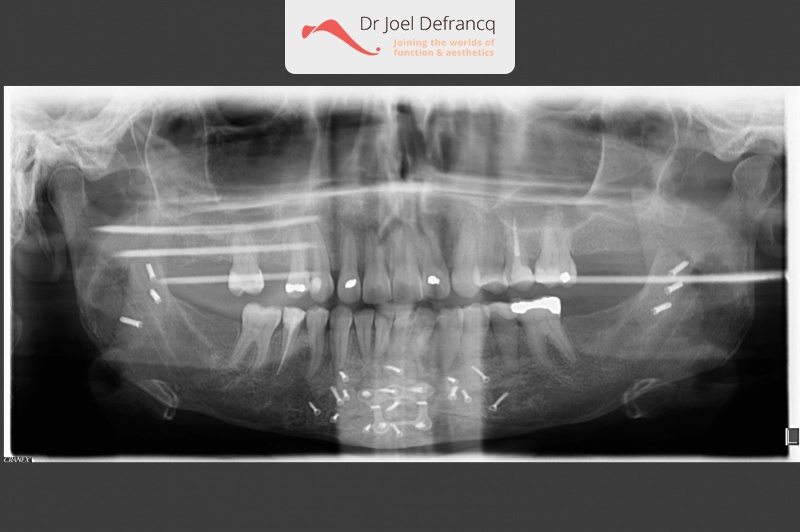

Dentale diagnose

- Klasse II divisie 1

- Diepe beet

Kaakchirurgie

- Verlenging onderkaak (BSSO)

- Kinchirurgie

- Onderrand shaving der onderkaak